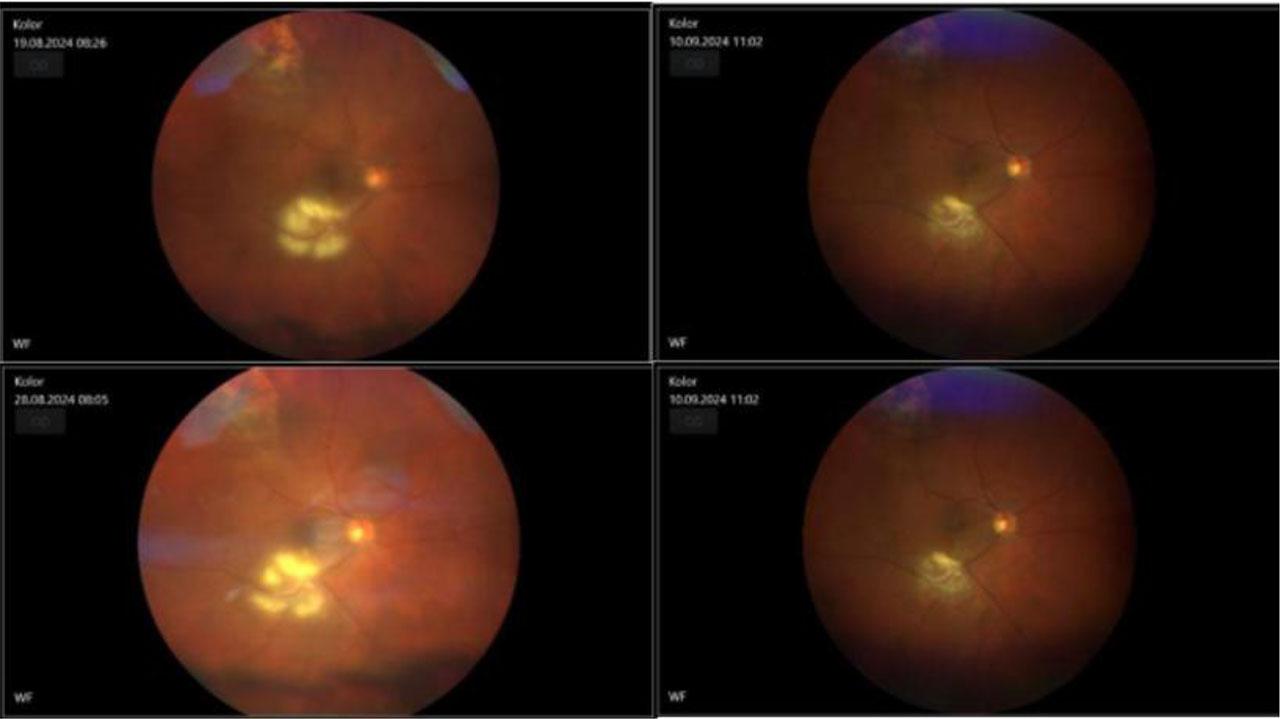

Figure 1.

Figure 2.

Figure 3.

Figure 4.

Figure 5.